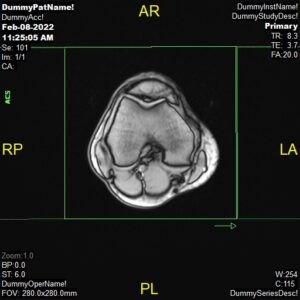

T2 Axial and PD FatSat Axial,

Parameters

Sample Image